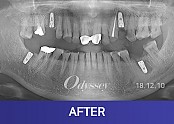

임플란트 181208